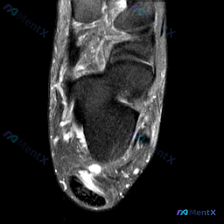

刚看到这张踝关节T2轴位MRI,我整理一下影像表现和分析思路,跟大家讨论一下。 病例影像基本信息 这是踝关节轴位T2加权MRI,液体呈高信号(亮白色),骨皮质、肌腱韧带呈低信号(黑色)。 先看基础结构: - 骨性结构:胫骨、腓骨、距骨截面可见,骨髓信号均匀,没有明显骨质破坏或异常骨髓水肿 - 肌腱结...